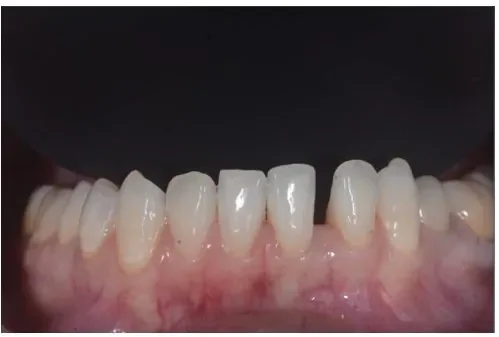

Before

After

ダイレクトボンディングの症例3

2週間、3回 / 66,000円リスク・副作用:経年的に歯間が開いてくる可能性及び接着低下によりレジン脱離、レジン周囲変色